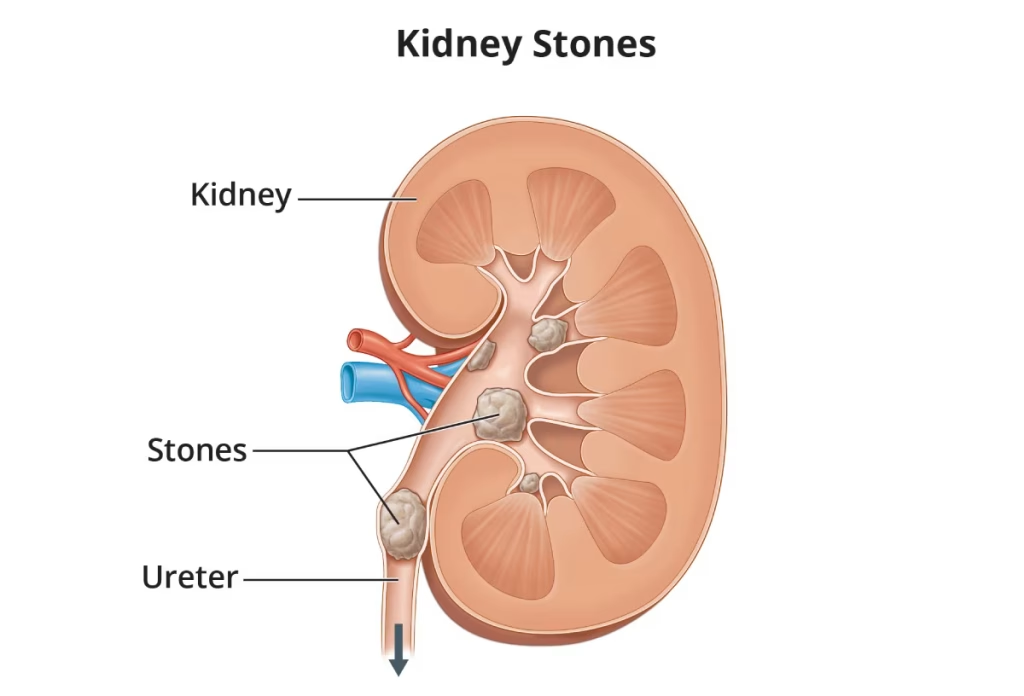

سنگ هاي کلیوي ذرات کوچک و سختی هستند که در یک یا در دو کلیه تشکیل شده و گاهی به داخل حالب ها ( لوله هاي عضلانی باریکی که ادرار را از کلیه ها به مثانه منتقل می کنند ) انتقال می یابند.

شناخت انواع سنگ ھای کلیه

سنگ کلیه شاخ گوزنی (stag horn)

علائم شایع سنگ کلیه که باید بدانید

درد شدید در قسمت پشت، شکم و یا کشاله ران

درد آھسته که از ناحیه کمر و لگن آغاز می شود.(این می تواند اولین نشانه وجود سنگ باشد. درد می تواند مداوم یا متناوب باشد. به ندرت پیش می آید که به طور کل از بین برود.

دردھای تیز و سوزن سوزن شدن در یک طرف کمر

ادرار مکرر و پرسوزش

خون در ادرار

کاھش دفع ادرار و یا قطع کامل آن

درد در ھنگام ادرار کردن

عوارض سنگ کلیه: چه مشکلاتی میتواند ایجاد کند؟

انسداد شدید مجاري ادرار